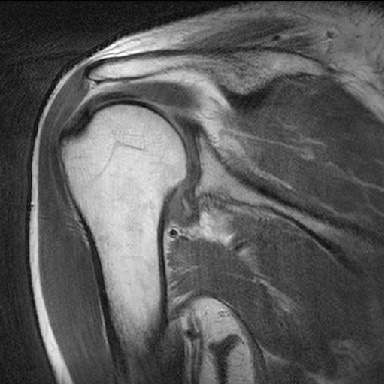

견관절낭염 환자의 방사선 영상

Rt.. Shoulder adhesive capsulitis